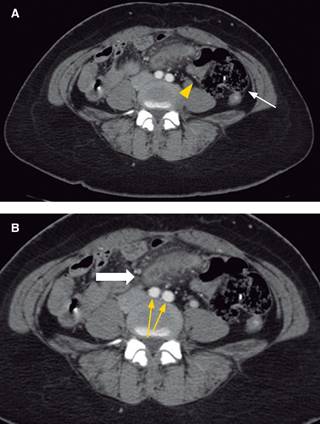

Figura 3: Imagen tomográfica en cortes axiales (A y B) a la altura de las arterias iliacas (flechas amarillas) mostrando en (A) a la válvula iliocecal (cabeza de flecha amarilla) y en (B) apéndice cecal en fase edematosa/supurativa (flecha blanca) en lado izquierdo de abdomen por mal rotación intestinal.